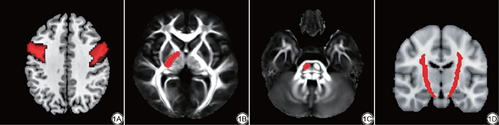

CST神经纤维束追踪研究通常选择的感兴趣区为中央前回(图1A),内囊后肢(图1B)和脑桥(图1C)[5,13-16]。从自动解剖标记(anatomical automatic labeling,AAL)模板上提取出标准空间下的中央前回模板,再通过配准的方法将其转换到被试个体空间[17]。内囊后肢和脑桥则由1名影像科副主任医师使用MRIcron软件在每个患者的FA图上确定。

首先使用BedPostX工具进行扩散参数的抽样贝叶斯估计,使用蒙特卡洛抽样方法建立每个体素的扩散参数分布,之后利用ProbTrackX工具进行概率性纤维束追踪,重建健康被试大脑双侧CST,最终生成健康被试CST模板[5,17-18]。具体做法是:在被试个体空间下,首先将同侧大脑半球内的中央前回、内囊后肢和脑桥分别设定为起始ROI、途经ROI和终止ROI,追踪出一束CST。然后将起始ROI和终止ROI互换,反向追踪出另一束CST,取两次追踪的重叠部分作为最终的目标CST。取平均的目的是减小误差,获得更精确的CST。接下来,将每个健康被试个体空间下追踪出的CST配准到标准空间下再次重叠并设置合适的阈值,最终得到健康被试组水平的CST[13, 14, 15, 16],即为健康被试的CST模板(图1D)。